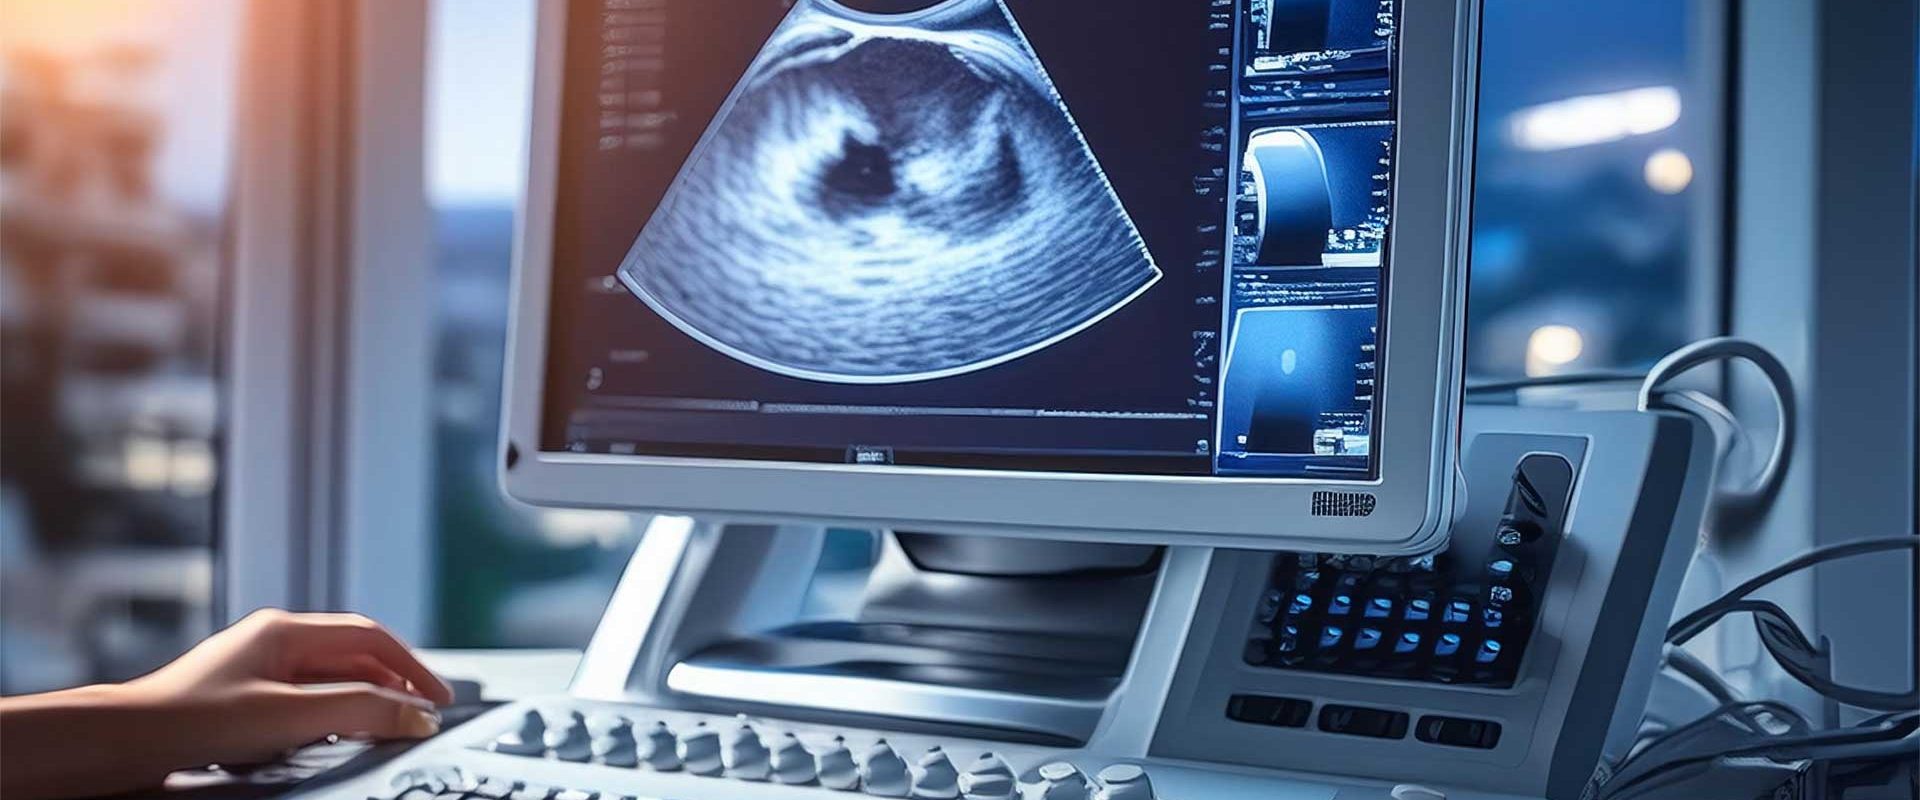

Un ecograf bazat pe inteligență artificială, aprobat pentru uz medical, promite acces sporit la imagistica prenatală

Un nou sistem de ecografie, bazat pe inteligența artificială (AI), a primit recent aprobarea pentru utilizare medicală. Dispozitivul, dezvoltat de Butterfly Network, utilizează un singur cip de siliciu pentru imagistica întregului corp, promițând o reducere a costurilor și o implementare mai ușoară în diverse unități medicale. Principalul său avantaj este potențialul de a îmbunătăți accesul la imagistica prenatală, în special în zonele cu resurse limitate.

Sistemul Butterfly funcționează diferit de ecografele tradiționale, care se bazează pe cristale piezoelectrice. Noua tehnologie utilizează un singur cip de siliciu, ceea ce simplifică designul și reduce costurile de producție. Compania susține că aparatul a fost „antrenat pe peste 21 de milioane de imagini ecografice”, provenite din diverse medii clinice și populații. Această bază de date extinsă este menită să asigure rezultate mai consistente.